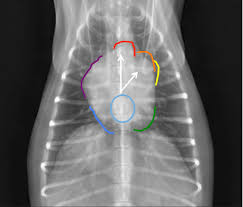

Carcinomas account for 97% of primary lung tumor in dogs with adc more prevalent and scc uncommon. Alveolar pattern observed in metastatic mammary and pulmonary neoplasia is due to confluence of smaller tumor nodules, hemorrhagic or necrotic reaction of lung parenchyma to tumor emboli, pulmonary edema secondary to airway obstruction by tumor, or extension of tumor into alveolar spaces + dogs. The second kind of lung cancer in dogs is called metastatic lung cancer, which means the cancer originated somewhere else in the body, but has spread to the lung. Most dogs with lung tumors present with coughing, exercise intolerance or other respiratory signs. Metastatic spread of primary lung tumors is generally to other areas of the lungs, tracheobronchial lymph nodes, bone, and brain.

Lung Cancer Canine Cancer from images.squarespace-cdn.com Certain breeds are more predisposed to develop pulmonary tumors than others. With pets living longer than ever, cancer has become a diagnosis that we see more commonly in older dogs. Secondary metastasis to the lungs is more common than primary canine neoplasm. Metastatic lung cancers (cancers that spread to the lungs from other locations) are much more common in dogs than primary lung cancers. The most common lung tumor seen in dogs is called a primary lung carcinoma and this arises from the tissues within the lung. The american veterinary medical association (avma) reports that one in four dogs will develop cancer at some time in their life and that 50% of pets over the age of 10 will develop cancer. Metastatic lung tumors usually present themselves as multiple masses. Other less specific signs include fever, lameness, and, in cats, vomiting.